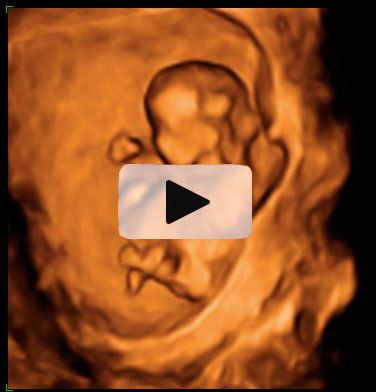

Ecografía 4D de la semana 12: Feto moviéndose de perfil

La ecografía 4D muestra al bebé moviéndose a sus anchas en el útero materno. Este plano de perfil muestra brazos, piernas y cordón umbilical en movimiento constante, lo que es es signo de vitalidad fetal. Las estructuras básicas de un feto de 12 semanas de gestación se parecen mucho a las de un bebé recién nacido; es ya todo un niño, aunque le falten unos seis meses aproximadamente para ver la luz.

Ecografía 4D: feto de 12 semanas moviéndose de perfil